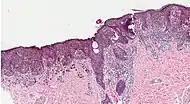

Melanoma in skin biopsy with H&E stain – this case may represent superficial spreading melanoma.

Following a visual examination and a dermatoscopic exam,[75] or in vivo diagnostic tools such as a confocal microscope, the doctor may biopsy the suspicious mole. A skin biopsy performed under local anesthesia is often required to assist in making or confirming the diagnosis and in defining severity. Elliptical excisional biopsies may remove the tumor, followed by histological analysis and Breslow scoring. Incisional biopsies such as punch biopsies are usually contraindicated in suspected melanomas, because of the possibility of sampling error[76] or local implantation causing misestimation of tumour thickness.[77][78] However, fears that such biopsies may increase the risk of metastatic disease seem unfounded.[79][80]